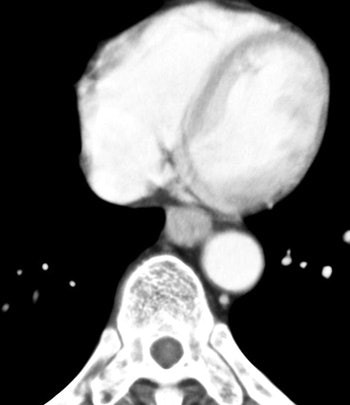

![]() |

| The arterial phase image of 64-year-old male with T3 esophageal cancer. In this case, the tumor is visualized as "wall thickening." The muscle layer cannot be seen. |